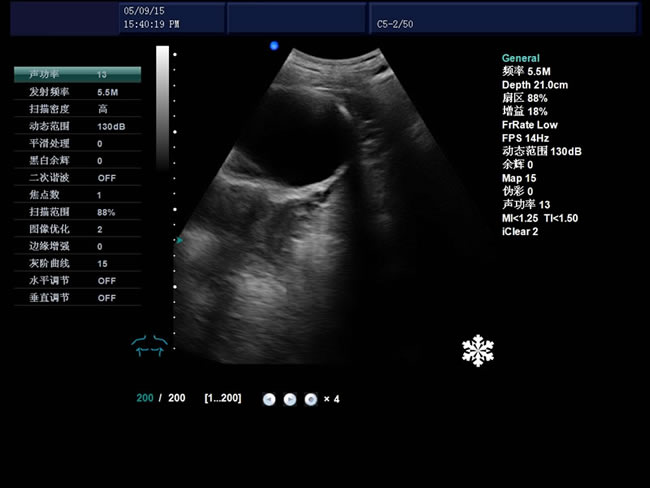

S8 彩色多普勒獸用超聲診斷儀

• S8彩色多普勒獸用超聲診斷儀是徐州市大為電子設(shè)備有限公司推出的一款全新的彩色超聲診斷儀器。

適用范圍:B超機(jī)產(chǎn)品性能

1、檢查母豬的空懷,降低無效飼養(yǎng)的功效早已深入人心

2、用B超監(jiān)測可及早準(zhǔn)確掌握妊娠母豬頭數(shù),較高的早期妊娠診斷準(zhǔn)確率較好的保證了均衡生產(chǎn)

3、探查時(shí)間短、無應(yīng)激、準(zhǔn)確率高,而且產(chǎn)生巨大的生產(chǎn)應(yīng)用價(jià)值